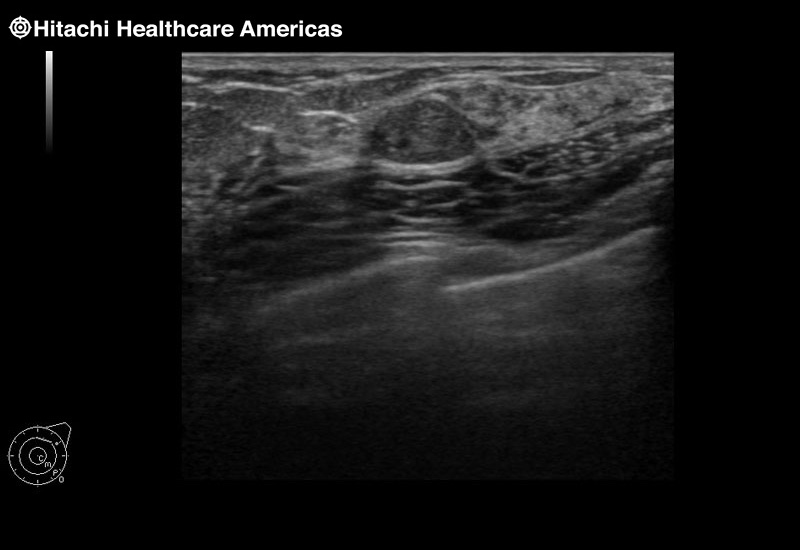

Superior guidance for all applications

Fujifilm Healthcare Americas is committed to designing tools that help surgeons navigate inside the human body and provide the necessary information to immediately make critical surgical decisions.

Fujifilm Healthcare's dedication to Surgeons provides outstanding ultrasound technology, professional support and the specialized tools necessary to best perform comprehensive real-time ultrasound imaging in Breast Surgery, General Surgery, Laparoscopic Surgery, Neurosurgery, Robotic Surgery and Surgical Oncology.

Recognized for our outstanding image quality, outstanding system reliability and intuitive use of cutting edge technology, Fujifilm Healthcare remains the standard in the field of Surgery.

Recognized for our outstanding image quality, outstanding system reliability and intuitive use of cutting edge technology, Fujifilm Healthcare remains the standard in the field of Surgery.